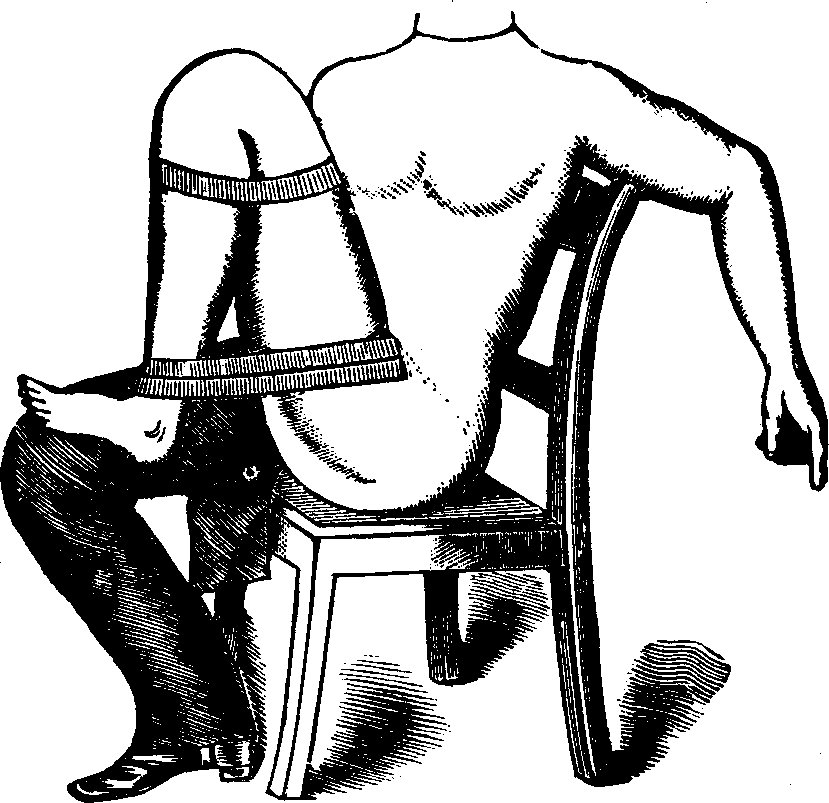

Fig. 5. STOHLMAN'S HYSTEROTOME. This instrument has two cutting blades

which shut past each other, as seen in the lower figure, so as not to cut

when introduced into the canal of the uterine neck. After introduction, the

cutting blades are separated, as shown in the upper figure, the extent of

the incision being regulated by the thumb-screw attached to the handles, as

represented in the lower figure.